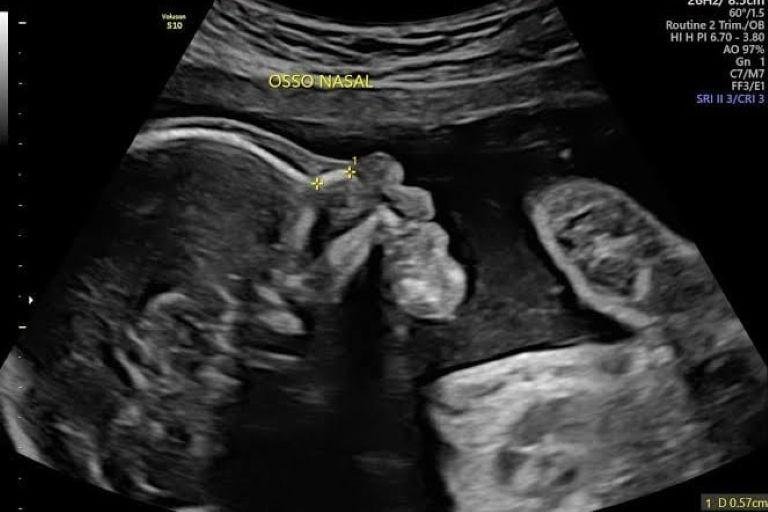

• Ultrassom Obstétrico

Acompanhamento completo da gestação com exames de alto e baixo risco, incluindo ultrassom obstétrico simples, com Doppler, Doppler com perfil biofísico fetal (PBF) e ultrassom morfológico do 1º, 2º e 3º trimestre.